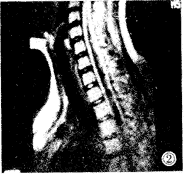

图2 空洞位于颈胸交界处,呈多囊样或分隔样改变